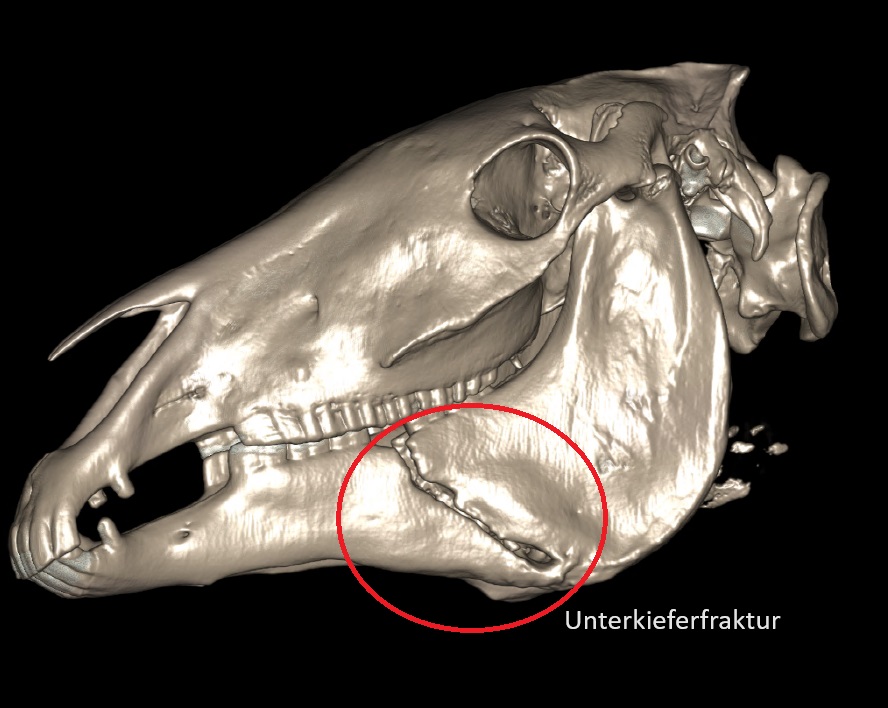

Alpaka